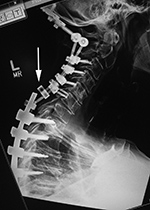

| 59 year-old man with past history of C3-5 fractures and extensive posterior spinal fixation from the occiput to T8. Lateral radiographs of the cervical spine three months apart show dislodgement (arrow) of the bilateral cervical posterior rods from connection with the thoracic rods at the C7-T1 level. Left: before dislodgement. Right: after dislodgement. After dislodgement there is increased kyphosis at the C6-7 level. |

From Hunter, 2004 |